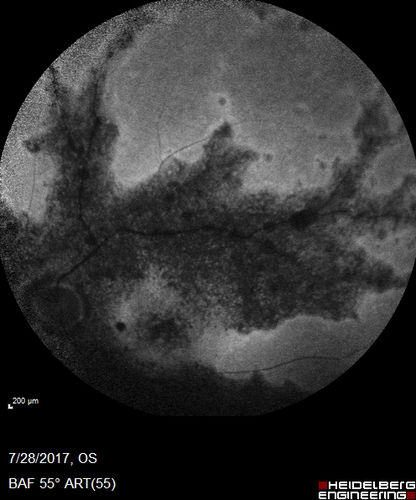

Pigmented Paravenous Retinochoroidal Atrophy - Left Eye

70 year old woman lost vision OS 20 years ago.